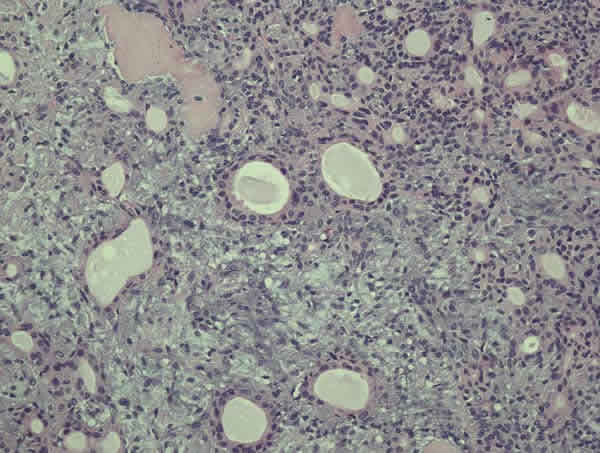

Se solicitó una tomografía con realce para hueso que mostraba una masa homogénea en la glándula lagrimal que comprimía el globo ocular, y no mostraba calcificaciones ni erosionaba el hueso. Tampoco producía remodelación ósea del hueso adyacente (fig. 2).

Fig. 2. TC con programa para hueso que demuestra una masa homogénea en región súperotemoral con ausencia de remolado ósea adyacente a la masa.

En nuestro caso, el TC mostraba ausencia de remodelación ósea (fig. 2), lo que, sumado a la presencia de un dolor leve (el dolor es un signo de mayor invasión y de malignidad por infiltración perineural (1,2,4), presente en un 10% aproximadamente de los adenomas pleomórficos) (2,4) sugería un origen maligno e implicó mayor rapidez para realizar la exéresis. La confirmación anatomopatológica y la exéresis completa con pseudocápsula cierran casi por completo la posibilidad de recidiva o conversión hacia carcinoma.